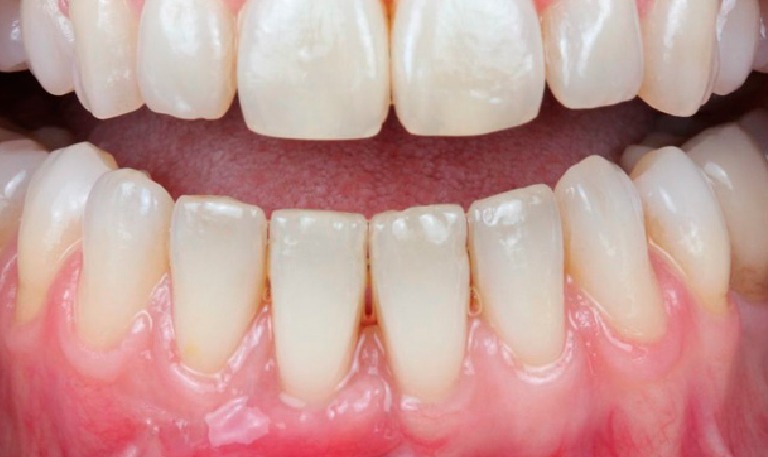

Blanqueamiento Dental

BeforeAfter